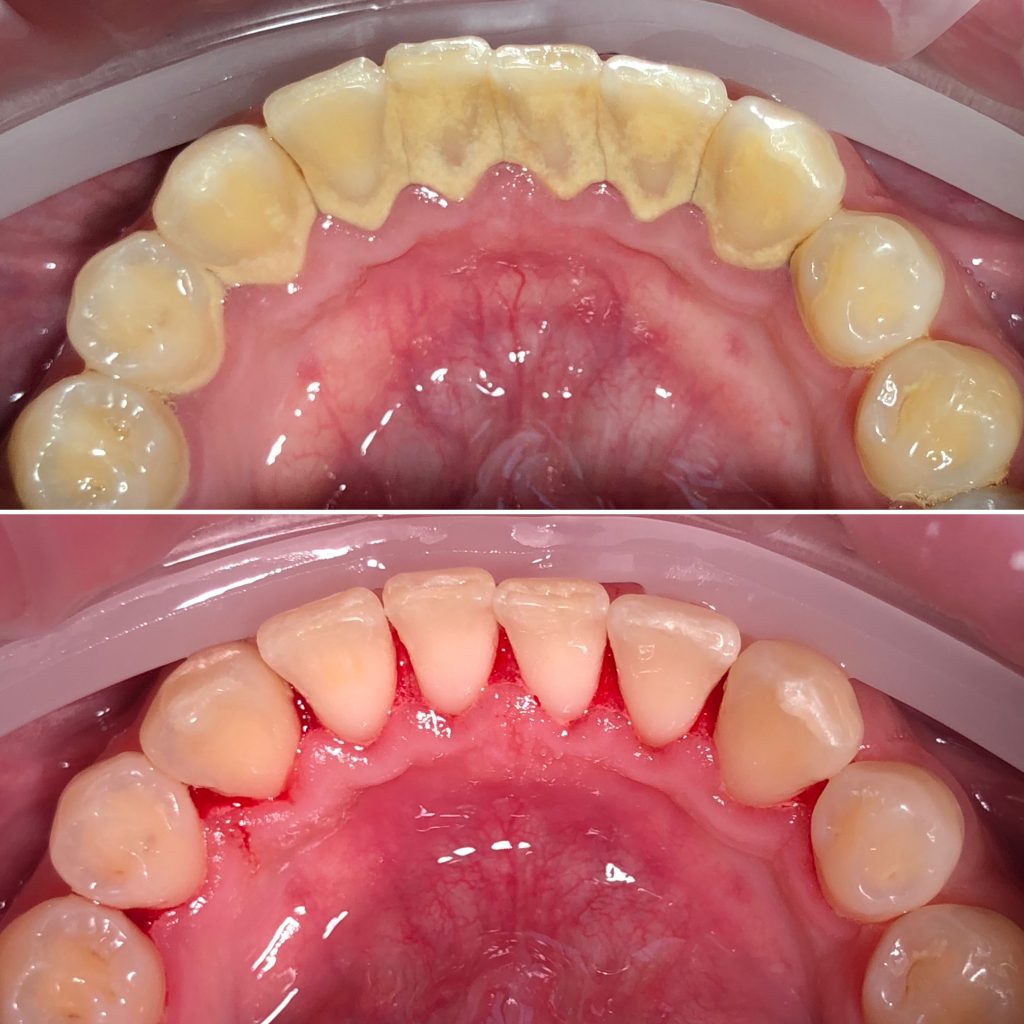

• Профессиональная гигиена полости рта и подбор индивидуальных средств гигиены, профилактика стоматологических заболеваний